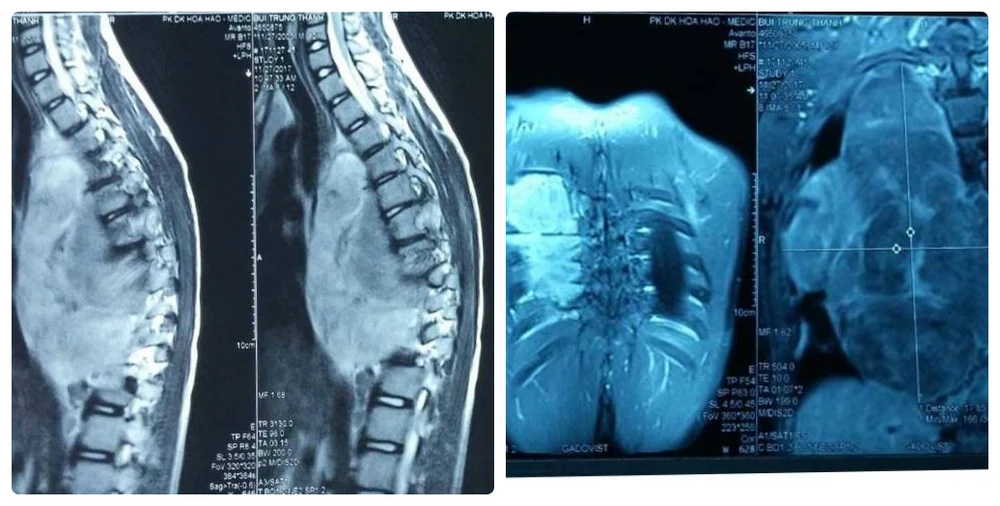

Phim chụp X-Quang cho thấy khối bướu khủng trong lồng ngực lan sang ống sống gây biến dạng cột sống.

Tại BV Nhi đồng 1, qua các xét nghiệm hình ảnh, bé T. được chẩn đoán có khối bướu khủng chèn ép chiếm toàn bộ mặt phổi bên trái, kích thước 18 x 13,5 x 9 cm và phát triển lan đốt sống, chèn ép lên tủy.

Đây là nguyên nhân khiến bé vẹo cột sống, tê yếu hai chân dưới. Sau khi nhập viện, tình hình sức khỏe bé giảm sút nhanh khi sức cơ chân từ 4/5 giảm xuống còn 1/5, liệt cứng hai chân, tiêu tiểu mất cảm giác.